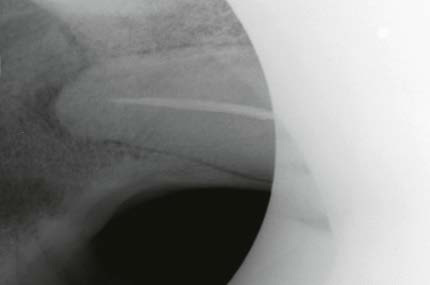

Obturation under extreme conditions

Every endodontic treatment is different. But when the patient weighs over 150 kg, the canines are 14 cm long and the treating physician has half an hour to work before he risks his life, GuttaFlow literally saves him from the mouth of the lion!